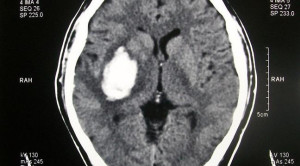

• Perdarahan Intraserebral Akut – Efikasi dan Keamanan Penurunan Tekanan Darah Intensif

Perdarahan Intraserebral Akut – Efikasi dan Keamanan Penurunan Tekanan Darah Intensif

Pada kasus perdarahan intraserebral akut, penurunan tekanan darah penting dilakukan karena tekanan darah tinggi berkaitan dengan risiko ekspansi hematoma dan luaran klinis...(Baca Selengkapnya)

• Andexanet untuk Perdarahan Intraserebral Akut Terkait Inhibitor Faktor Xa – Telaah Jurnal Alomedika

Andexanet untuk Perdarahan Intraserebral Akut Terkait Inhibitor Faktor Xa – Telaah Jurnal Alomedika

Andexanet for Factor Xa Inhibitor–Associated Acute Intracerebral Hemorrhage Connolly SJ, Sharma M, Cohen AT, et al; ANNEXA-I Investigators. Andexanet for Factor Xa...(Baca Selengkapnya)

• Target Tekanan Darah pada Pasien dengan Pendarahan Intraserebral Akut

Target Tekanan Darah pada Pasien dengan Pendarahan Intraserebral Akut

Target tekanan darah pada penatalaksanaan pendarahan intraserebral akut atau acute intracerebral hemorrhage (ICH) mungkin dapat mempengaruhi outcome ICH. Definisi ICH adalah kerusakan...(Baca Selengkapnya)